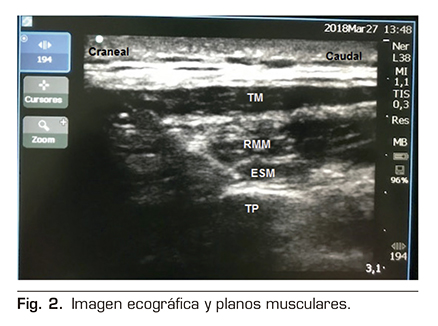

Figura 2